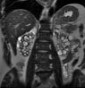

Liver Disease

Ronald N. Rubin, MD

<div id="article-content-body"> <p>Routine blood work revealed liver function abnormalities in a 55-year-old woman. She had recently undergone extensive dental work that resulted in...